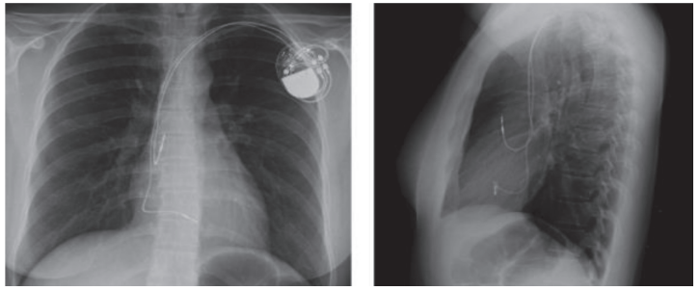

Uma paciente de 68 anos com doença do nódulo sinusal e síncope foi submetida a implante de marcapasso definitivo. De acordo com a sua radiografia de tórax, assinale a opção que representa o tipo de

dispositivo implantado.